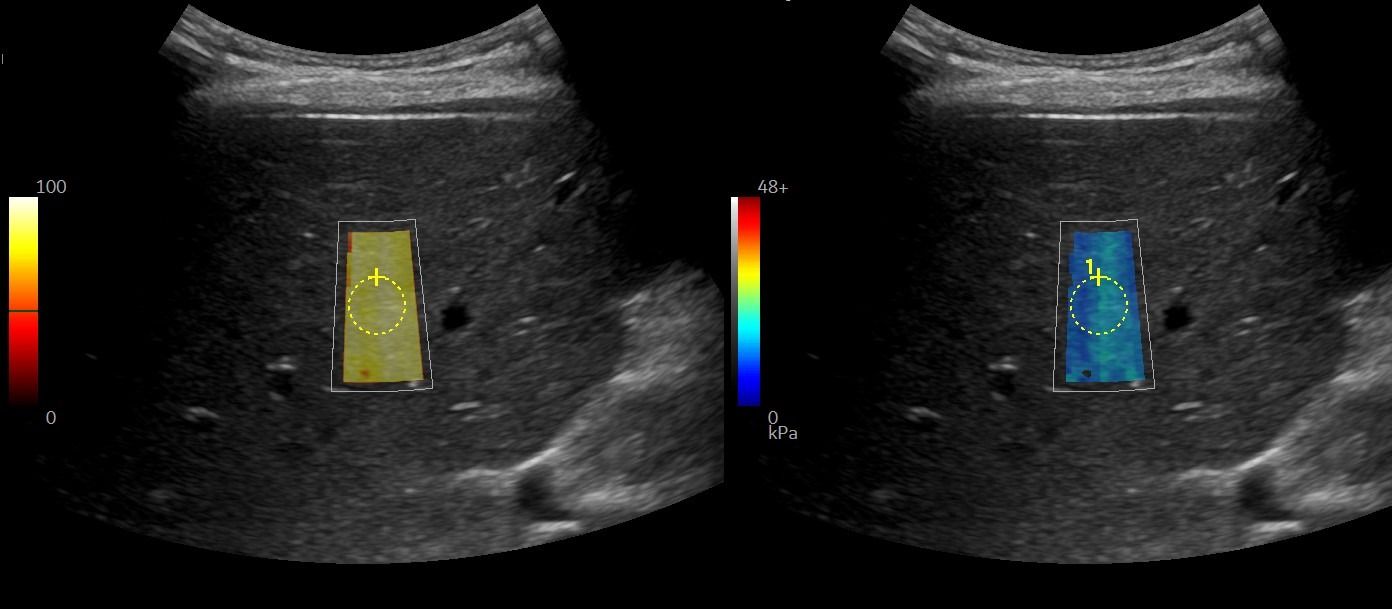

Με την Eλαστογραφία Ήπατος γίνεται αξιολόγηση της ελαστικότητας του ήπατος και υπολογισμός του βαθμού λιπώδους διήθησης ή/και ίνωσης, σε περίπτωση χρόνιας ηπατοπάθειας.